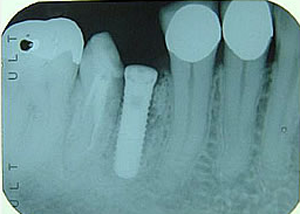

右下

第一第臼歯近心根破折

(大臼歯は歯根が二つに分かれている)

1.H18.4.12

抜歯後

(某歯科医院にて手前の歯根のみ抜歯)

2.インプラントする前

(抜歯後4ヶ月弱)

3.H18.8.22

抜いたところにインプラント埋入